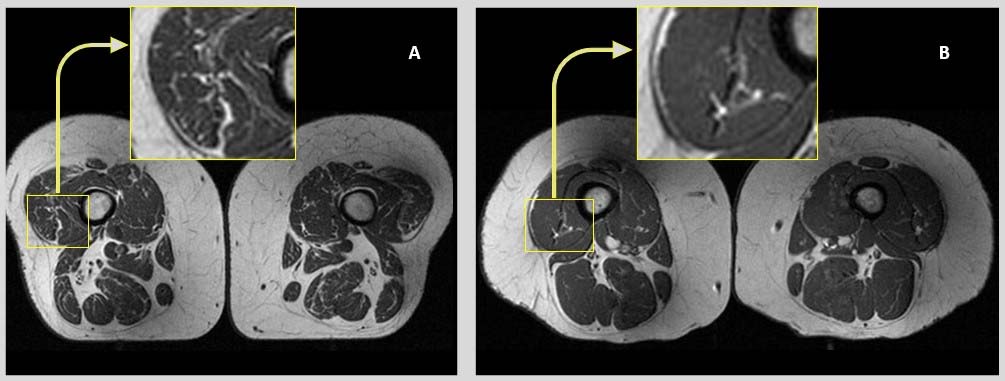

Εικόνες μαγνητικής τομογραφίας από τις πλευρικές πτυχές των τετρακέφαλων μηριαίων μυών δύο γυναικών που συμμετείχαν στη μελέτη, ηλικίας 58 (Α) και 62 ετών (Β). Στη γυναίκα Α, της οποίας η διατροφή αποτελείτο κατά 68% από υπερεπεξεργασμένες τροφές, οι μηριαίοι μύες παρουσιάζουν πολλές λιπαρές ραβδώσεις. Στη γυναίκα Β, που η διατροφή περιείχε μόνο 36% υπερεπεξεργασμένα τρόφιμα, οι μύες των μηρών παρουσιάζουν λιγότερες λιπαρές ραβδώσεις.

CREDIT: Radiological Society of North Aurora (RSNA) and Zehra Akkaya, M.D.